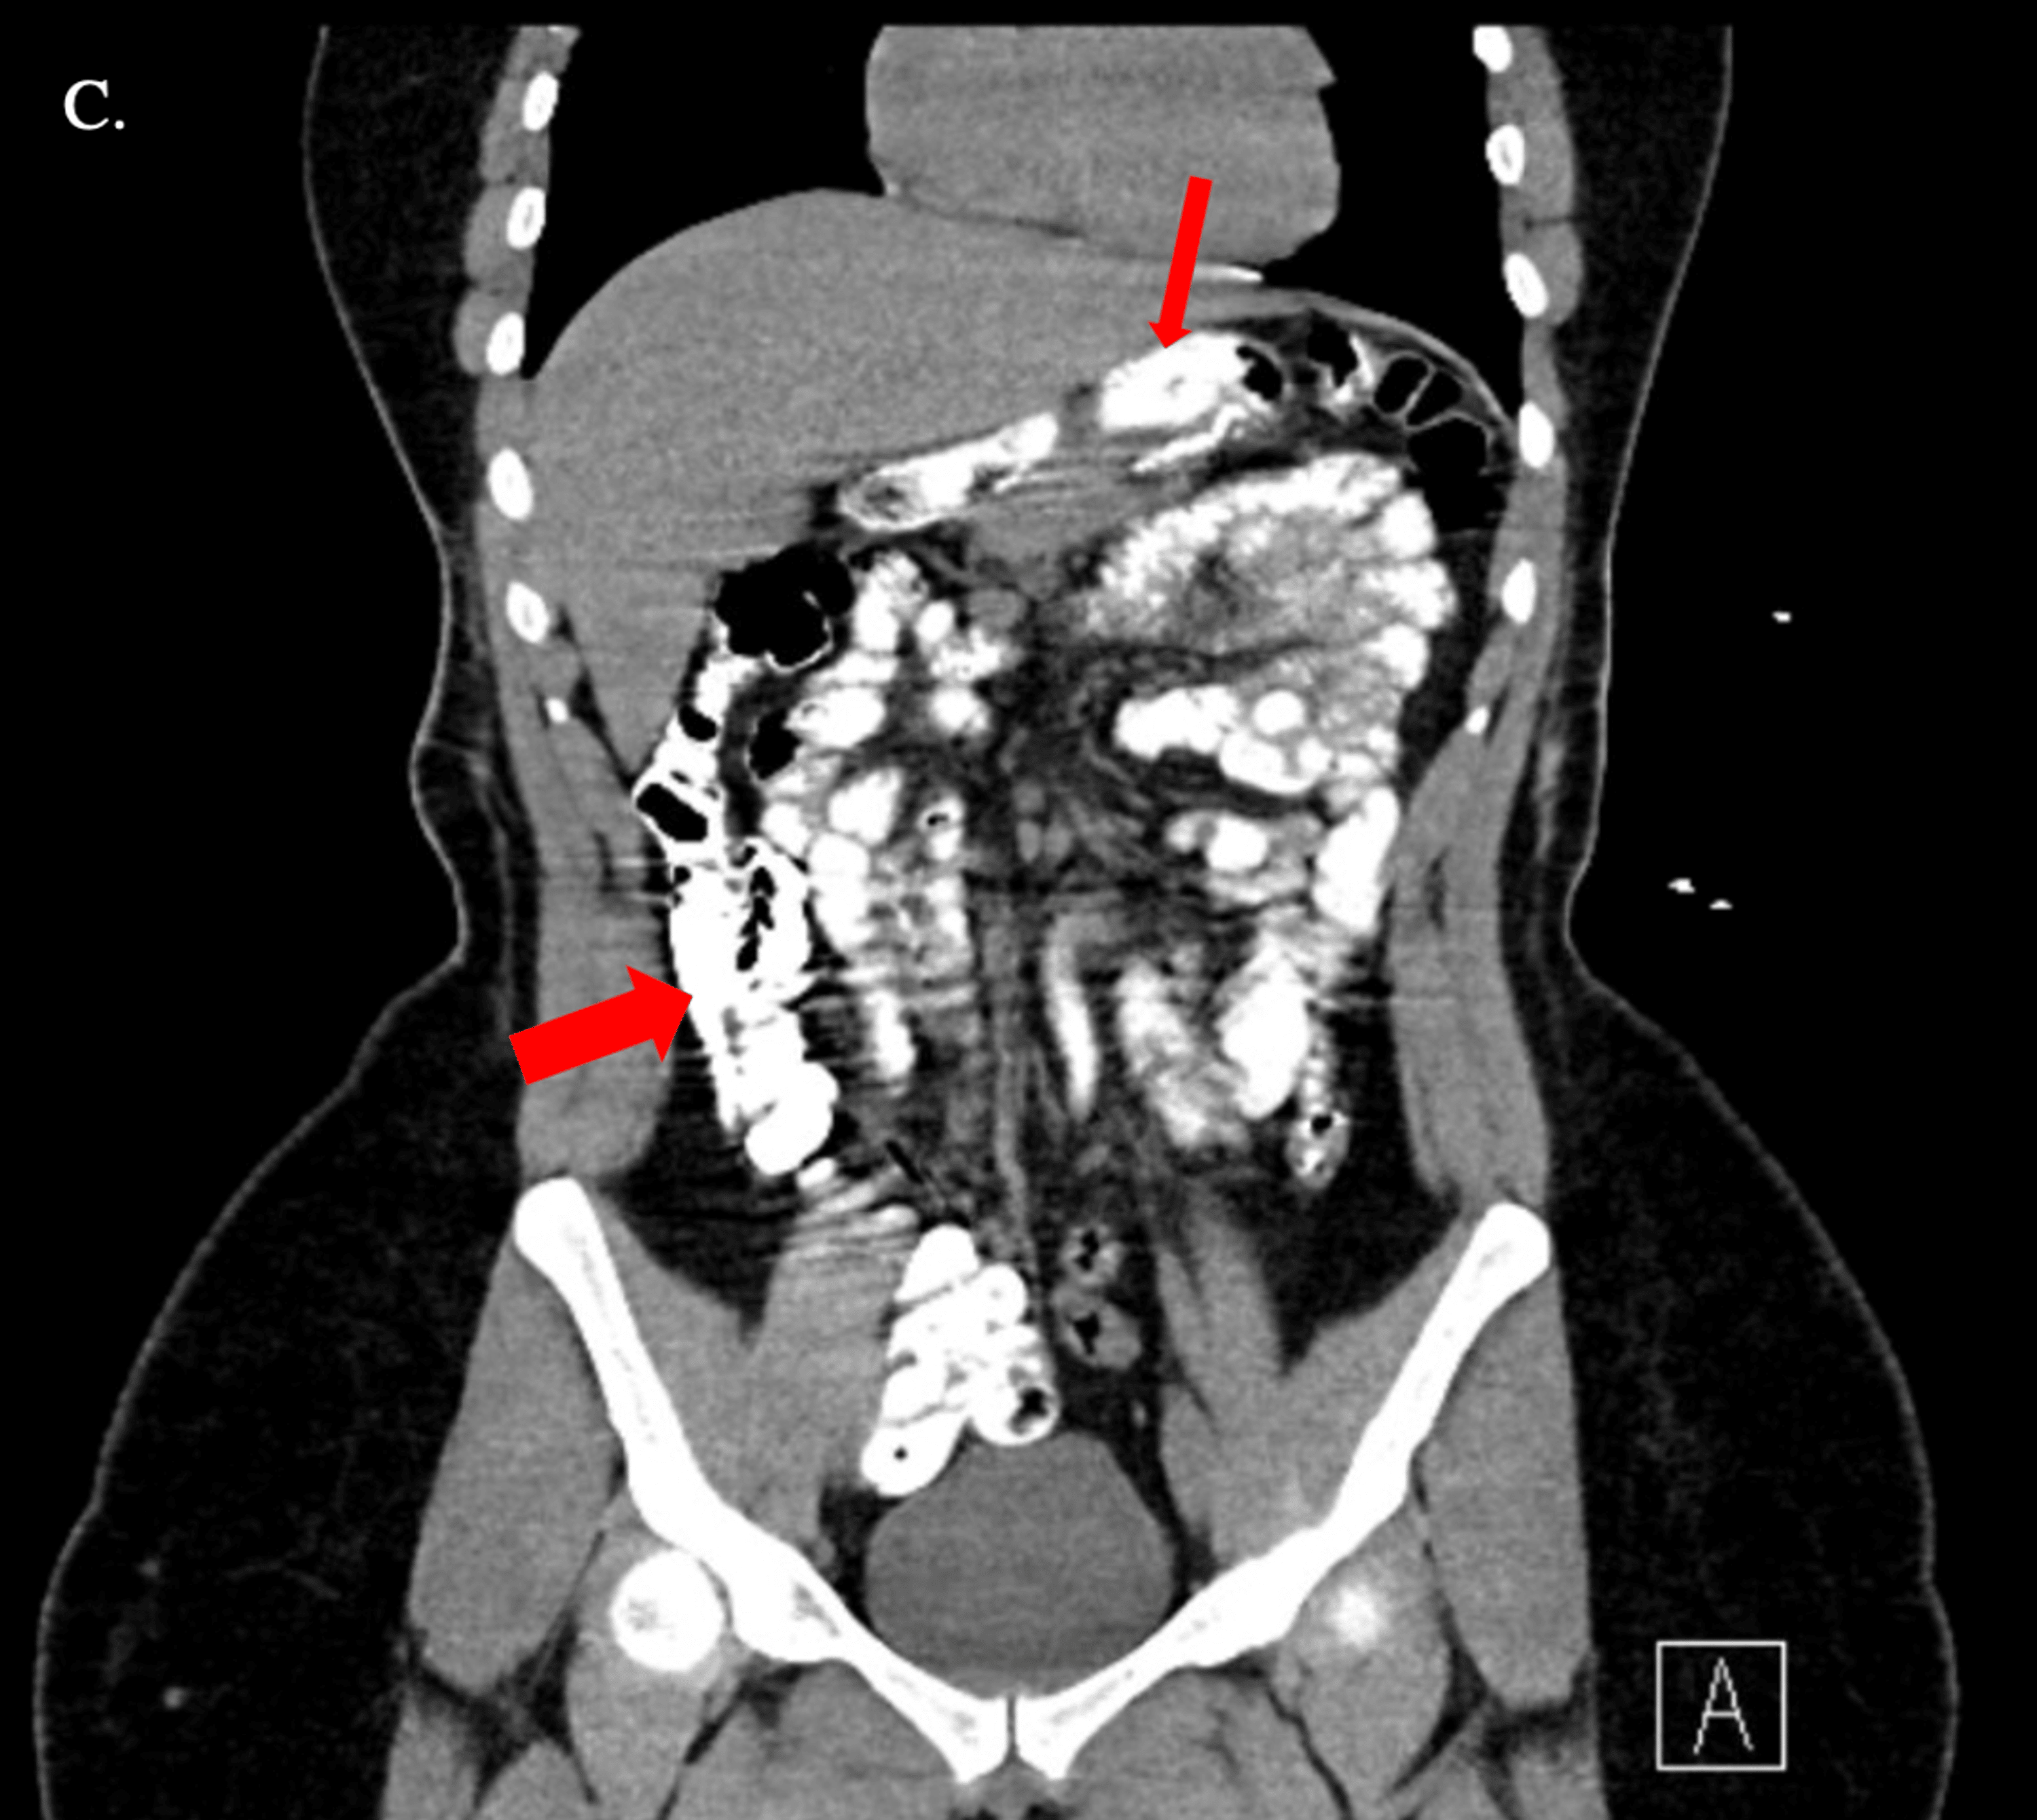

Figure 1 from Delayed Presentation of Gastric Volvulus with Gastric Outlet Obstruction after Gastric Volvulus Post Sleeve Gastrectomy Gastric volvulus after sleeve gastrectomy is a rare entity presenting vague symptoms and signs and requires a high index of suspicion from the. After undergoing gastric sleeve surgery, it is important to be aware of the risk factors and potential causes that can lead to a twisted stomach, also known as gastric volvulus. It is crucial to recognize both common. Gastric Volvulus Post Sleeve Gastrectomy.

Figure 25 from Imaging of bariatric surgery normal anatomy and postoperative complications Gastric Volvulus Post Sleeve Gastrectomy Gastric volvulus is characterized by rotation of the stomach along its long or short axis leading to variable degrees of gastric outlet. Gastric volvulus after sleeve gastrectomy is a rare entity presenting vague symptoms and signs and requires a high index of suspicion from the. After undergoing gastric sleeve surgery, it is important to be aware of the risk factors. Gastric Volvulus Post Sleeve Gastrectomy.

Figure 1 from Intrathoracic sleeve gastrectomy migration with gastric volvulus treated with Gastric Volvulus Post Sleeve Gastrectomy Gastric volvulus after sleeve gastrectomy is a rare entity presenting vague symptoms and signs and requires a high index of suspicion from the. We are reporting a case of gastric volvulus post laparoscopic sleeve gastrectomy, which was managed conservatively. After undergoing gastric sleeve surgery, it is important to be aware of the risk factors and potential causes that can lead. Gastric Volvulus Post Sleeve Gastrectomy.

(PDF) Intrathoracic sleeve gastrectomy migration with gastric volvulus treated with laparoscopic Gastric Volvulus Post Sleeve Gastrectomy It is crucial to recognize both common and unusual complications of sleeve gastrectomy to properly diagnose and manage. After undergoing gastric sleeve surgery, it is important to be aware of the risk factors and potential causes that can lead to a twisted stomach, also known as gastric volvulus. Gastric volvulus after sleeve gastrectomy is a rare entity presenting vague symptoms. Gastric Volvulus Post Sleeve Gastrectomy.